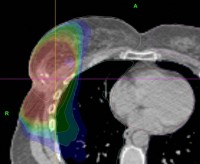

Arc-Based Radiation Therapy

External beam radiation machines have been undergoing steady modification and improvements. One of the most recent exciting advances is Eleckta's VMAT – volumetric arc therapy. Rather than using fixed beam angles to treat a tumor, VMAT allows the machine to swing in an arc, offering more precision and control of the radiation dose. Presently this technology is offered at several of our radiation centers. We were one of the very first groups of physicians to use VMAT in the United States and are involved with research and training for Eleckta's new technologies.